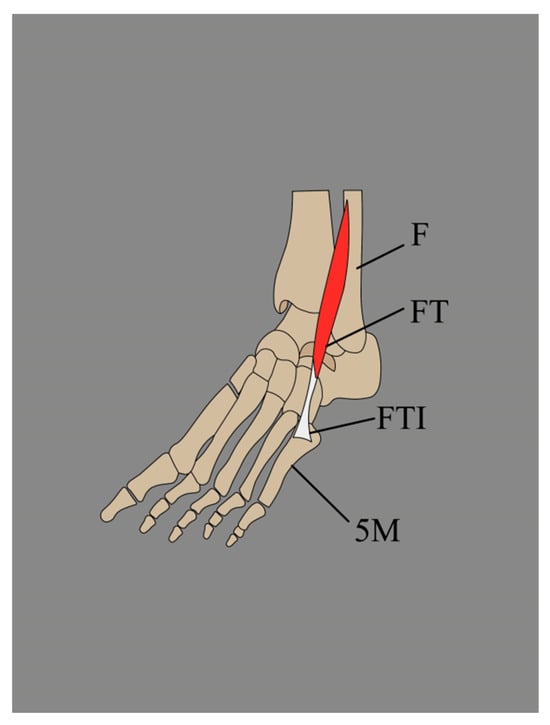

3.1. The Fibularis Tertius (FT) Typical Descriptive and Functional Anatomy

3.1.1. Typical Descriptive Anatomy

3.2.2. Variations in the Origin of the Fibularis Tertius (FT)

3.2.3. Variations in the Insertion of the Fibularis Tertius (FT)